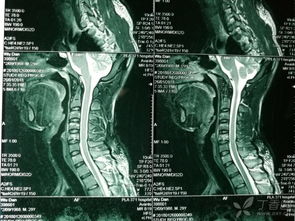

因為頸骨骨折也就是頸部脊椎骨的骨 折,在脊椎骨中央有神經(jīng)通過,這些神經(jīng)像電纜一樣能把大腦的命令傳達到全身,又能把身體的感覺傳向大腦。如果骨折切斷或壓迫脊椎骨中的神經(jīng),頸以下就會完 全麻痹,有時會使呼吸停止。

3、頸椎骨折常見于跳水誤跳入淺游泳池,或從很高的地方墜落以及交通事故等。

體位護理和體溫監(jiān)測 保持頭、頸、肩一致性活動,防止頸椎錯位。翻身時要一個人固定頭部,一個人搬動軀干,并注意顱骨牽引,防止滑脫,保持牽引繩與軀干在同一軸線上,床頭抬高15°~30°。顱骨牽引鋼針口處滴75%酒精4~5滴,每日更換敷料一次。由于脊髓損傷,植物神經(jīng)功能紊亂,全身交感神經(jīng)支被切斷,不能適應周圍環(huán)境溫度的變化而出現(xiàn)高熱,病人一旦出現(xiàn)高熱,體溫>38.5℃(腋下),即給予物理降溫,必要時給4℃冰生理鹽水300ml低壓灌腸,采取積極措施降溫。